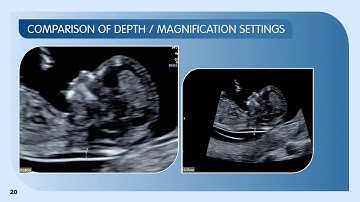

How to Measure Nuchal Translucency (NT) On Ultrasound | First Trimester NT Screening | Fetal USG